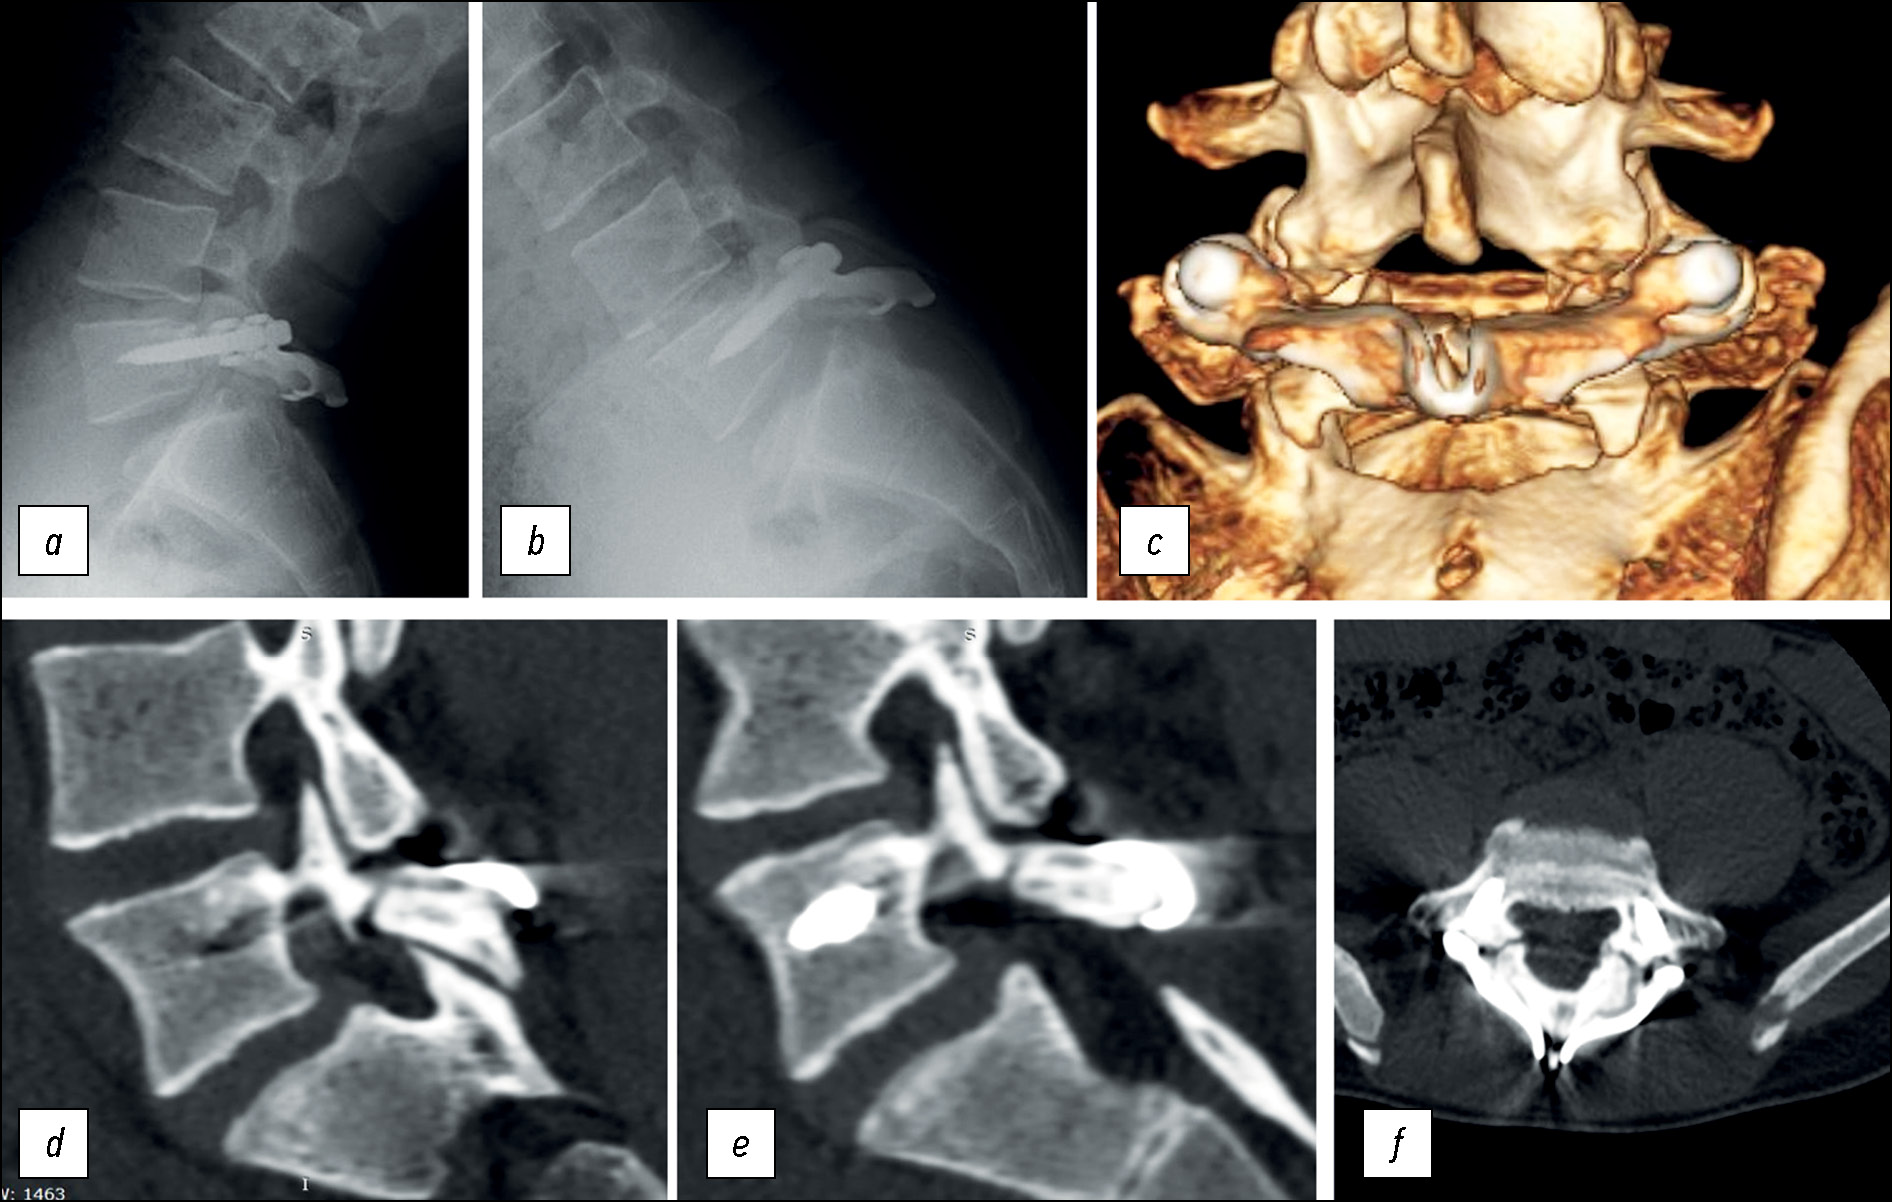

Рис. 1. Данные лучевой диагностики: а — постуральная рентгенография позвоночника в боковой проекции, b, c, d — компьютерная томография, e — магнитно-резонансная томография.

Fig. 1. Radiological imaging: a — postural radiography of the spine in lateral projection, b, c, d — computed tomography, e — magnetic resonance imaging.

Пациентке проведена лучевая диагностика. По данным рентгенографии позвоночника подтверждён спондилолиз L5 позвонка. Параметры сагиттального баланса туловища, по данным постуральной рентгенографии, без значимых отклонений от нормы (PI=60°, PT=14°, SS=46°, LL=65°, TK=38,5°) (рис. 1а).

По данным мультиспиральной КТ пояснично-крестцового отдела позвоночника определяется билатеральный спондилолизный дефект межсуставной части дужки L5 позвонка (рис. 1b, c, d). По данным МРТ пояснично-крестцового отдела позвоночника, признаки стеноза позвоночного канала отсутствуют, гидрофильность межпозвонковых дисков не нарушена (рис. 1e).